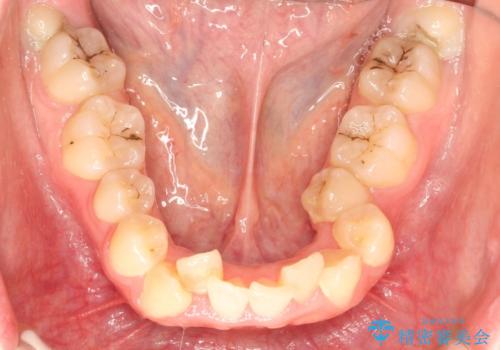

- 上下の全体的ながたつきが気になるとのことで来院されました。

上下左右の前から4番目の歯を抜歯をして、ワイヤー矯正にて並べる計画としました。

患者様が装置を早期に除去したいという希望もあり、少々下の前歯のがたつきが残った状態で矯正を終了しました。